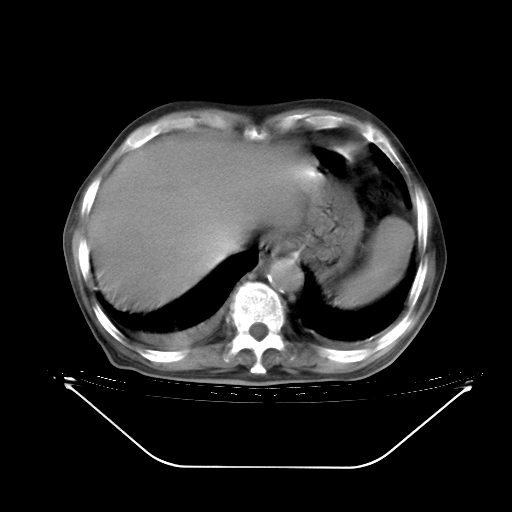

胸腹部CT,诊断意见:左上肺叶钙化灶、左侧胸膜局限性增厚并钙化、胆囊炎。描述部分肺组织呈磨玻璃样改变。

今天复查肺部CT,发现双肺广泛磨玻璃样改变。所以我把3月19日和5月9日相隔50天的肺部CT上传。请大家会诊。

5月9日肺部CT(在4月27日齐鲁医院肺部CT描述部分肺组织磨玻璃样改变,12天后肺组织广泛磨玻璃样改变)